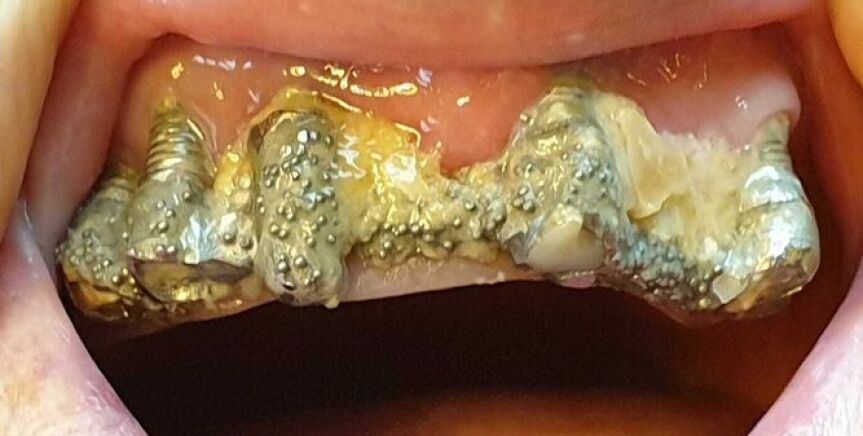

Cuenta que acudió por primera vez a la clínica en 2010 para colocarse implantes dentales en la parte superior de la boca, pero que el dentista le recomendó hacerlo también en la mandíbula inferior. Así, le extrajeron todos los dientes para susituirlos por piezas de porcelana, pero los implantes se deterioraban, se rompían y se infectaban constantemente. Por ello, le realizaron numerosas reparaciones y le recolocaron la prótesis varias veces, causándole lesiones en la boca.

Asegura que los arreglos que le hicieron en las coronas rotas a veces "duraban menos de una hora" y que, en 2016, tras más de 80 visitas al centro donde fue atendida por una decena de profesionales distintos, la clínica le comunicó que no se haría cargo de más reparaciones. A partir de entonces tendría que asumir el coste ella misma.

La mujer dice que trató de llegar a un acuerdo con el centro, pero no fue posible, por lo que denunció. Uno de los peritos que la examinó, contratado a título particular, determinó que le habían realizado "una verdadera chapuza" en la boca.